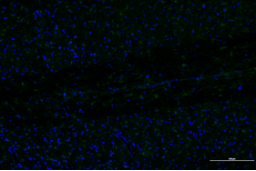

正常對(duì)照組 模型組

脊髓損傷模型GFAP表達(dá)差異對(duì)比

免疫熒光技術(shù)是將免疫學(xué)方法(抗原抗體特異結(jié)合)與熒光標(biāo)記技術(shù)結(jié)合起來研究特異蛋白抗原在細(xì)胞內(nèi)分布的方法。由于熒光素所發(fā)的熒光可在熒光顯微鏡下檢出,從而可對(duì)抗原進(jìn)行細(xì)胞定位,并且可以通過熒光強(qiáng)度對(duì)檢測蛋白的表達(dá)量進(jìn)行半定量分析。